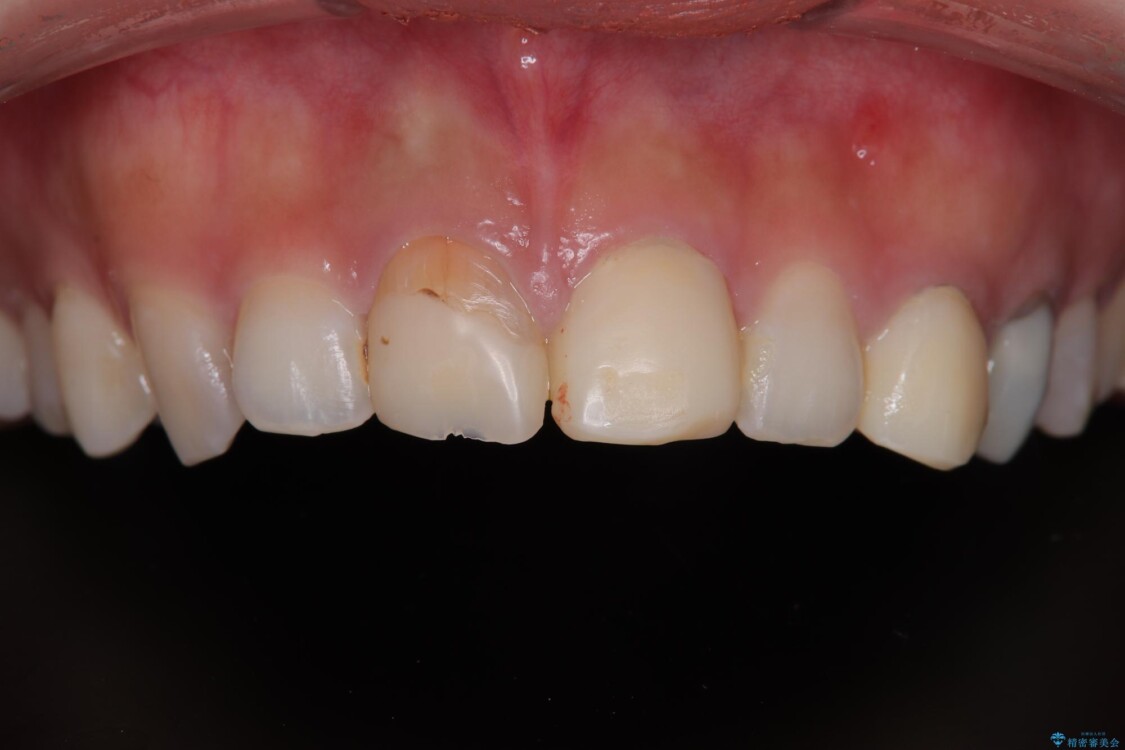

治療前

• 「抜歯してブリッジ」と言われた20代女性が選んだ治療とは|たった4か月で自然な笑顔に抜歯即時インプラント+審美補綴の症例 治療前画像

20代女性の患者様。 他院にて「上の前歯(右上中切歯)は抜歯してインプラントかブリッジにする必要がある」と診断され、大変ショックを受けられていました。 すでに根管治療を受けた歯でしたが、急に担当医が変わり、「抜歯が必要」とだけ説明されたことに不安感を抱き、当院を受診されました。 左上中切歯と犬歯も仮歯のままで、将来への不安が大きかったご様子です。

精密検査の結果、右上中切歯には**フェルール(歯の周囲の健全な歯質)**がほぼ存在せず、このままの状態での保存は困難と判断しました。